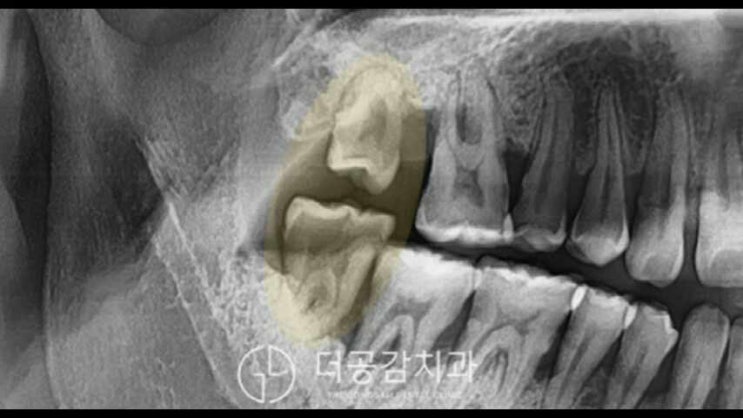

치주질환의 경우 방치하면 치아가 뽑힐 수 있으므로 주의가 필요하다. 야탑치과의원 치주질환은 건강한 구강환경을 파괴하여 결국 여러 개의 치아를 사용할 수 없게 되는 질환으로 치수에 세균감염이 원인이기도 하지만 흡연, 운동부족, 면역력 저하 등의 영향을 받기도 하므로 건강한 생활습관으로 관리하고 있습니다. 계속해야합니다.

흔히 풍치라고 알려진 야탑치주질환은 치석이 잇몸으로 퍼져 염증으로 발전해 잇몸뼈가 파괴되는 질환이다. 심하고 방치할수록 잇몸뼈가 녹아 치아가 흔들리거나 여러 가지 특징을 보일 수 있기 때문에 꾸준한 관리가 필요한 치주질환입니다. 치주질환의 원인은 다양하지만 입안에 쌓이는 치석이 치주질환을 유발할 수 있습니다.

치석은 입 구석구석에 침착되어 잇몸을 압박하여 잇몸을 후퇴시키고 결과적으로 목이 마모되고 치아의 목이 움푹 패이게 됩니다. 이러한 상황을 미연에 방지하기 위해서는 정기적인 야탑치과 검진이 필요하며, 치아교정과 대면상담을 통해 치주질환을 조기에 예방하고 치료할 수 있습니다.